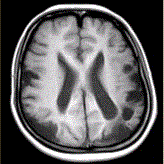

问题 女性,22岁。癫痫发作及智力异常。MRI显示见下图。 为进一步明确诊断,下一步的影像学检查首选

选项 A.MRI增强 B.FLAIR C.DWI D.MRA E.MRV F.DSA

答案 D